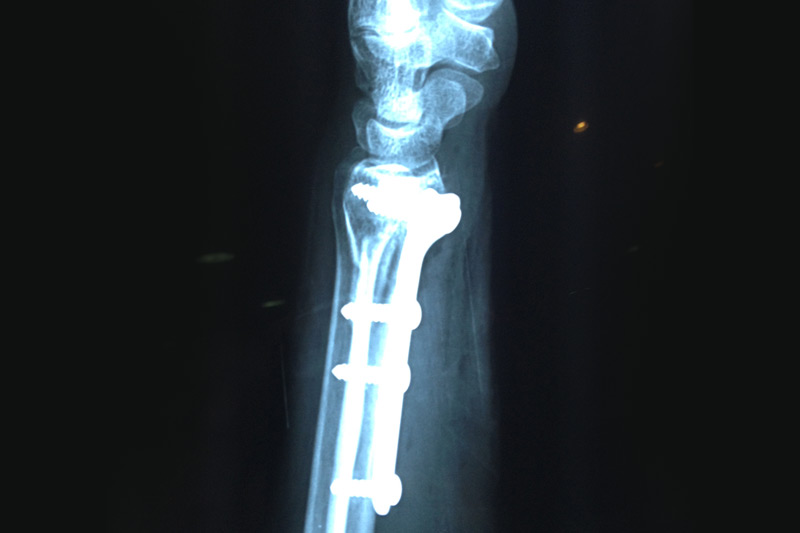

Dentro del avance en medicina se incluye la cirugía artroscópica, su característica es la mínima invasión, se realizan portales ( incisiones ) menores de 8 mm, por el cual se realizan cirugías ortopédicas con la finalidad de restaurar la congruencia articular, obteniendo excelentes resultados incluyendo ausencia de dolor y una pronta reincorporación a sus actividades cotidianas.